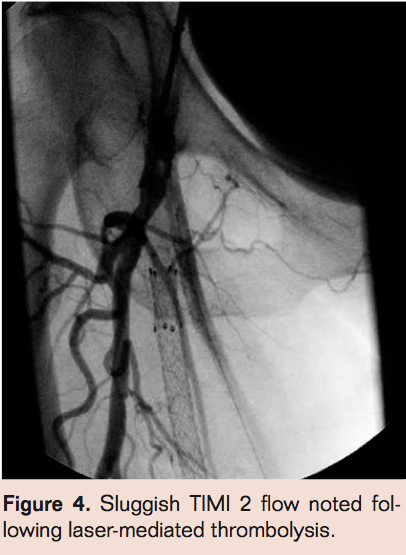

- Laser thrombectomy at 1 mm/sec. with the 2.3 mm probe (Figures 4-9)

- Repeat angiography, and if there is no obvious thrombus proceed to definitive therapy. If there is no flow, then perform angiography via side hole perfusion catheter placed across the occlusion to determine residual thrombus. Patients with residual thrombus are treated with TNK infusion via infusion catheter at 0.5 mg/hr. Repeat angiography at 3 hours to assess patency. If necessary, perform prolonged lytic infusion followed by definitive therapy.

Complete angiographic resolution of thrombus and definitive therapy was achieved in 51 of 78 patients (65.3%) during the index angiographic procedure in the angiographic suite. In 12 of 78 patients (15.3%) flow was established in the index procedure but there was residual thrombus necessitating continued lytic infusion. Of those 12 who had residual thrombus, 11 had complete resolution of thrombus following 3 hours of lytic therapy allowing definitive therapy in the same day. No flow was established during the index procedure for 15 of 78 patients (19.2%). Of these patients angiography via the side hole perfusion catheter showed substantial resolution of thrombus but enough residual thrombus to obstruct antegrade flow in 14 of 15. There was no evidence of thrombus resolution in 1 of 15 patients for whom no flow was established in the index procedure. Of those 15 patients,3 (20%) had complete resolution of thrombus at 3 hours post angiography while 12 of 15 patients (80%) required prolonged lytic infusion. Graft patency was established in 78 of 78 patients but bleeding complications were much less common in the group with successful index procedure than those requiring overnight infusion (2% vs 47% with major bleeding necessitating transfusion of 2 units of PRBC’s in 2 patients who had overnight lytics).